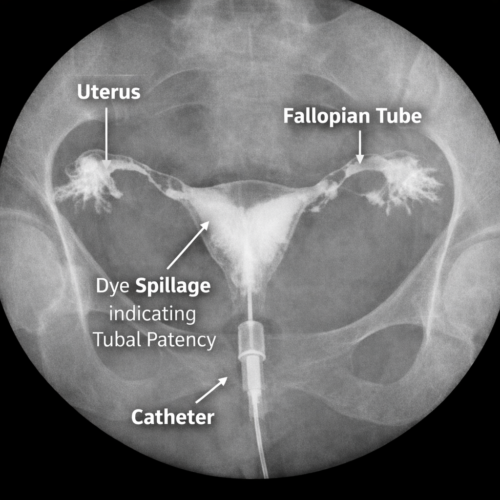

HSG is an X-ray based imaging test that uses a special contrast dye to visualise the uterine cavity and fallopian tubes. As the dye flows through the tubes, fluoroscopic X-rays capture detailed images. If the tubes are open, the dye will spill through the tube ends — indicating patency. If there’s blockage or abnormal anatomy, the flow will be disrupted.